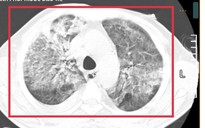

Điều trị bệnh nhân mắc bệnh Whitmore còn gọi là bệnh "sốt đất" tại Bệnh viện Bạch Mai. Ảnh minh họa

Biểu hiện ở bệnh nhân Whitmore